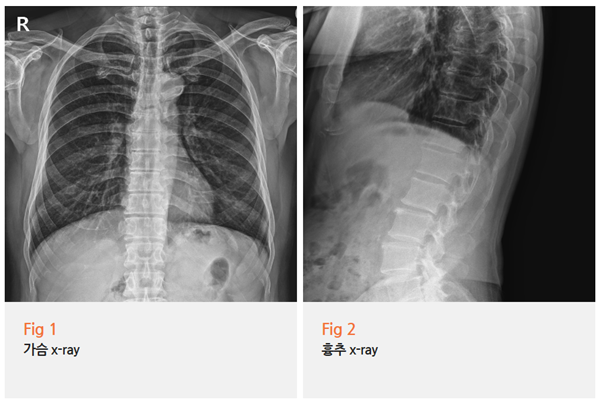

심전도? 정상.

심초음파? 정상.

흉부 X-ray? 정상.